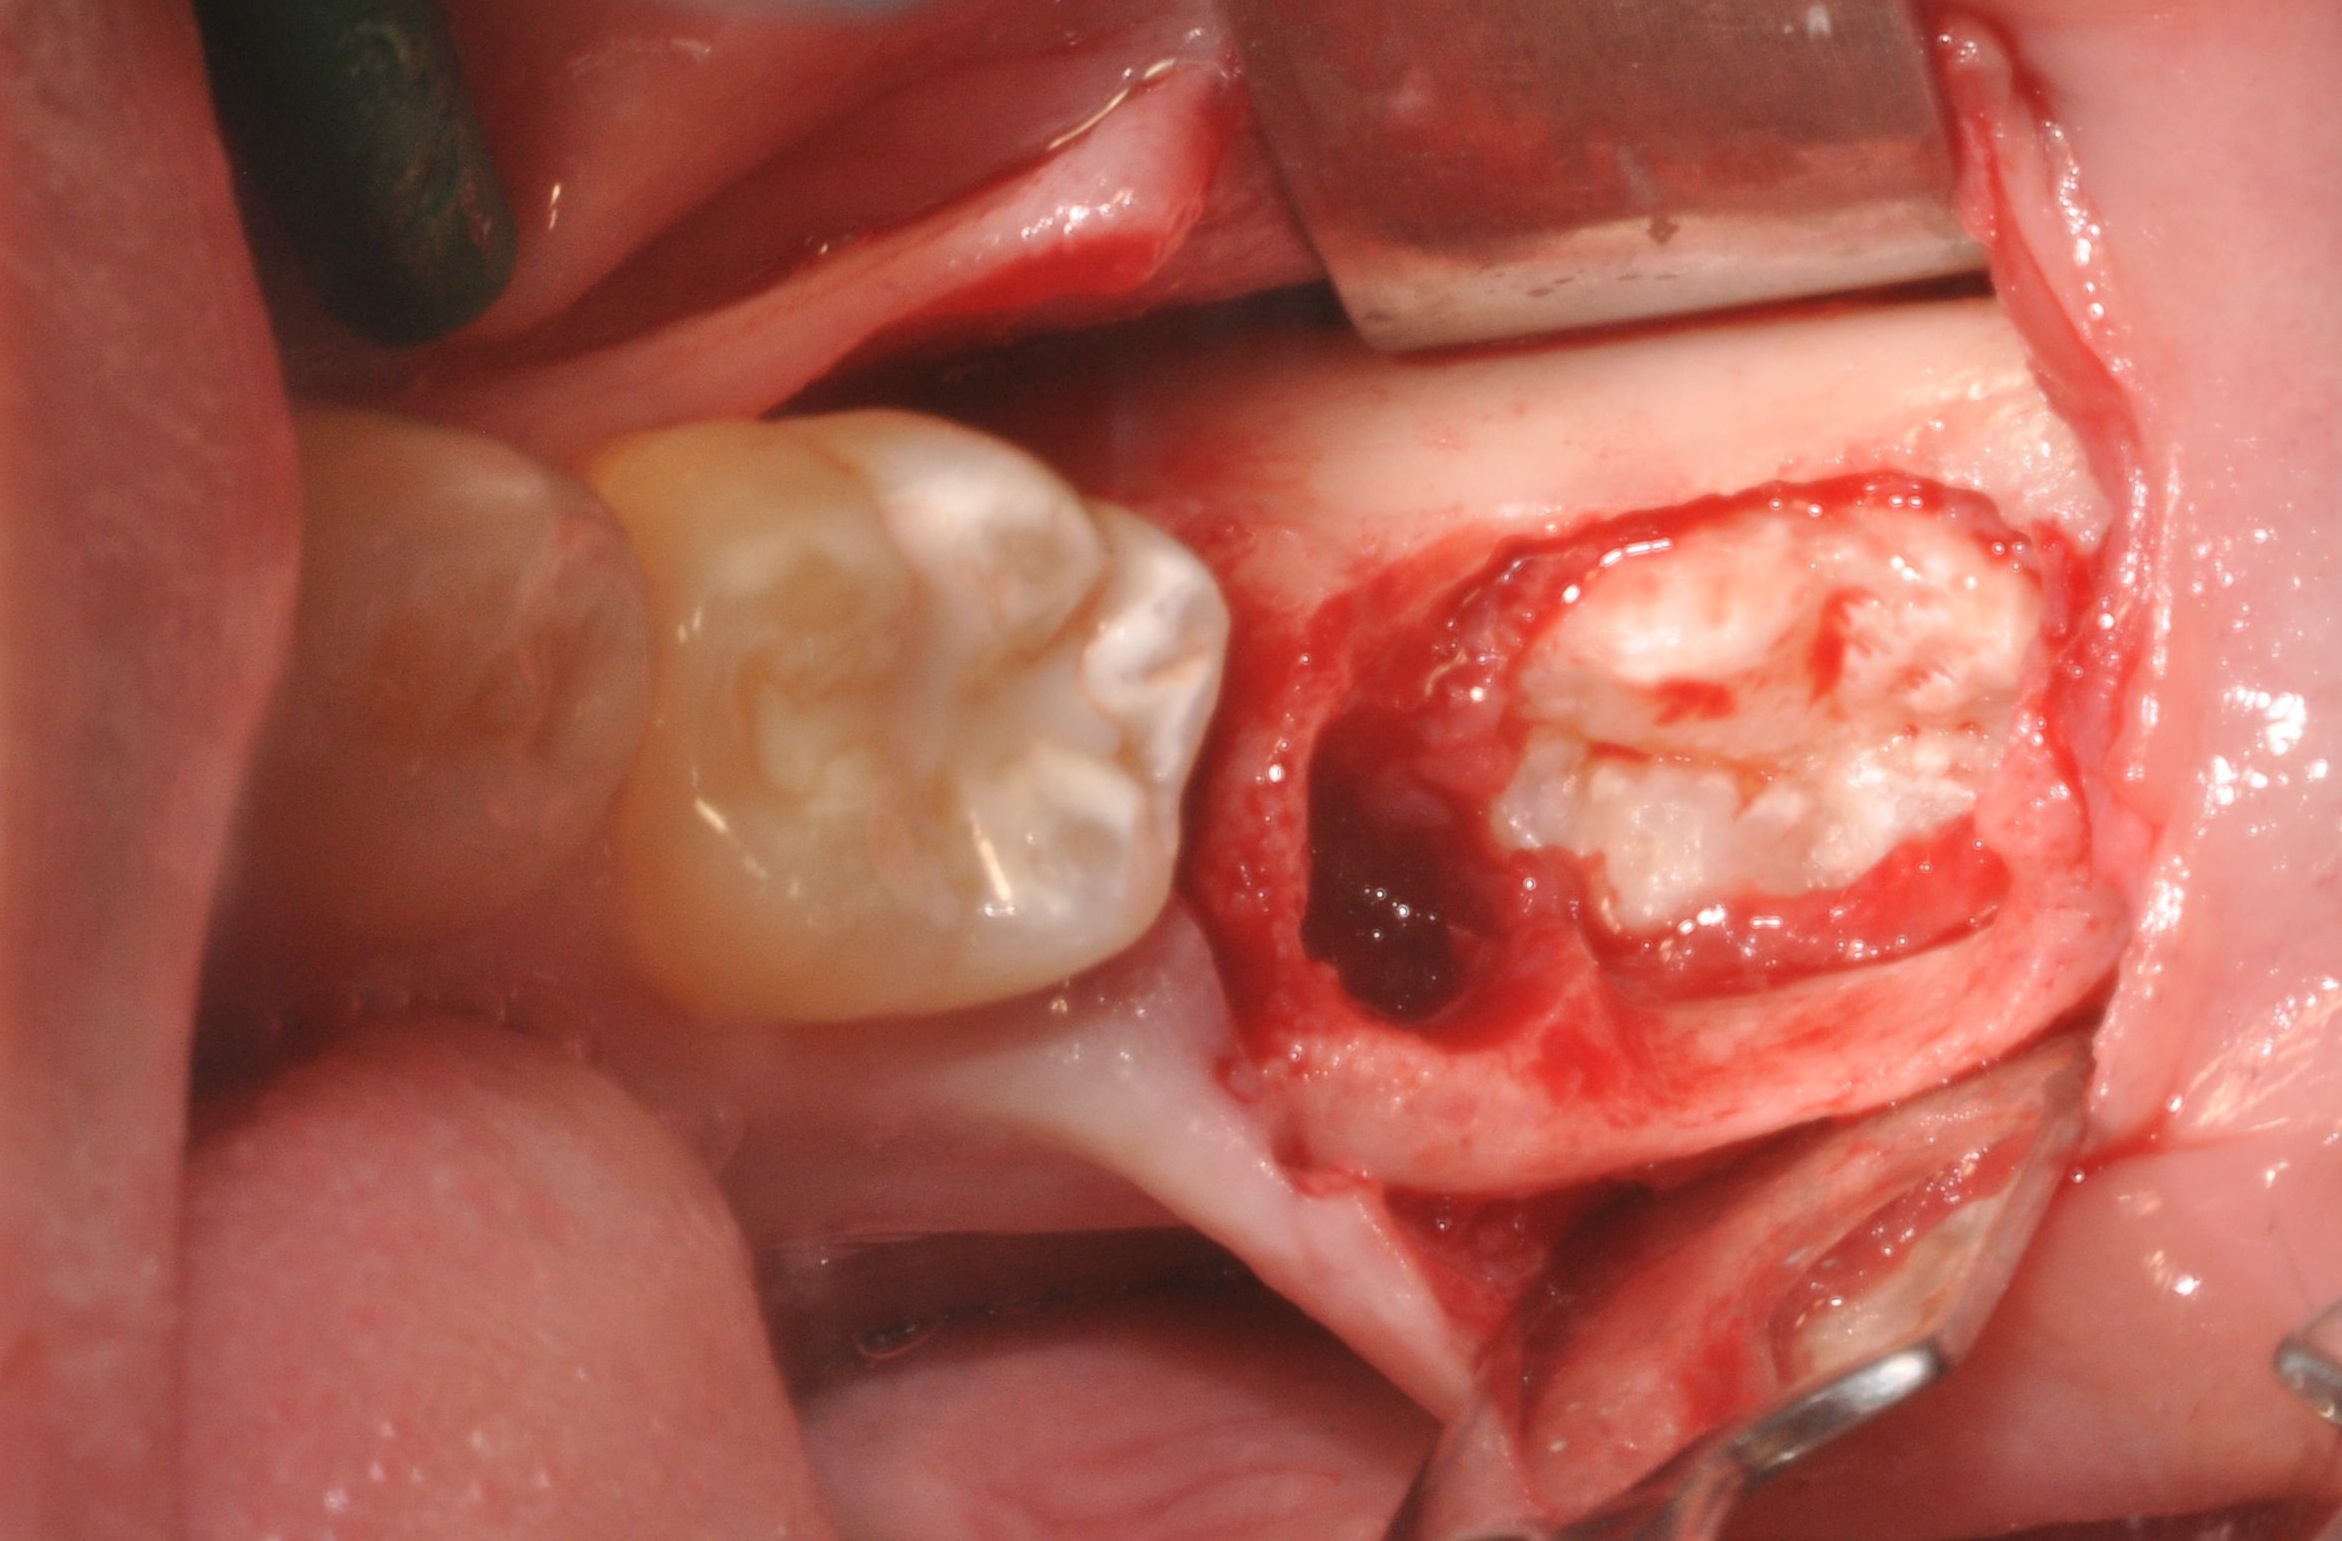

Data la giovane età del paziente e la conseguente impossibilità ad eseguire un impianto dentale, si decide di eseguire l’ estrazione del molare in questione e contestualmente di trapiantare al suo posto un dente del giudizio precedentemente in totale inclusione ossea, presente nella zona limitrofa.

L’ elemento trapiantato viene stabilizzato per 21 giorni mediante splintaggio fisso e monitorizzato radiograficamente.